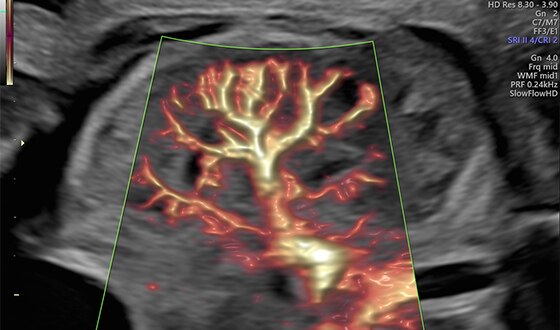

Circle of Willis shown with SlowflowHD in Dual Display